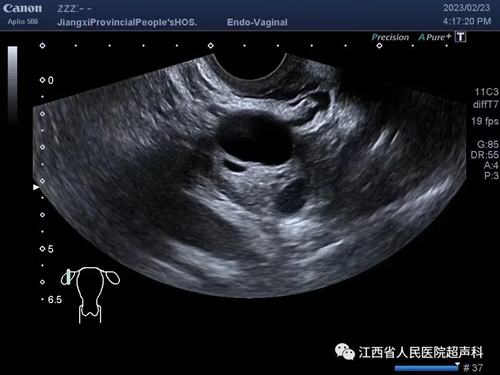

超声检查是卵巢囊肿最常用的检查方式,有性生活史者建议首选经阴道超声检查,无性生活或囊肿过大超出盆腔也可选择腹部超声检查。超声显示囊肿呈囊性无回声、囊壁薄、无实性成分、无分隔及血流信号者称为单纯囊肿。